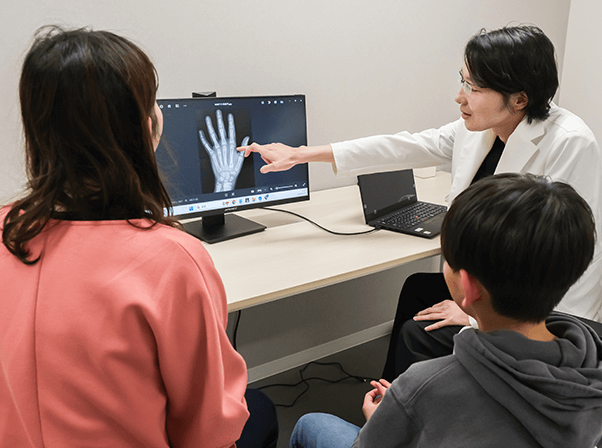

まずは、正確な評価から

成長ホルモン療法の適否を見極めるためには、現在のお子さまの成長段階を医学的に正確に把握することが何よりも重要です。当院では、最新の画像解析技術とAIを組み合わせた評価システムを導入し、従来よりも安全かつ高精度な診断を可能にしています。

低負担X線装置による骨年齢評価

お子さまの手のX線画像で「骨端線」の状態を確認し、骨年齢を測定します。使用するのは医師監修のもと独自開発した低負担のX線撮影機器で、身体への配慮を重視した設計です。撮影は左手のみで行うため、負担を抑えた検査が可能です。 お子さまの安全を第一に考えた検査体制を整えています。

AIによる骨年齢解析システム

取得したX線画像は、AIによる高度な画像解析技術により数値化され、骨年齢と今後の成長予測を導き出します。このシステムは、医師の目視による主観的な評価に比べ、精度・再現性ともに非常に高く、診断の客観性を大きく向上させるものです。医師の診断にAIのデータを掛け合わせることで、より的確な成長評価・治療計画が可能となります。